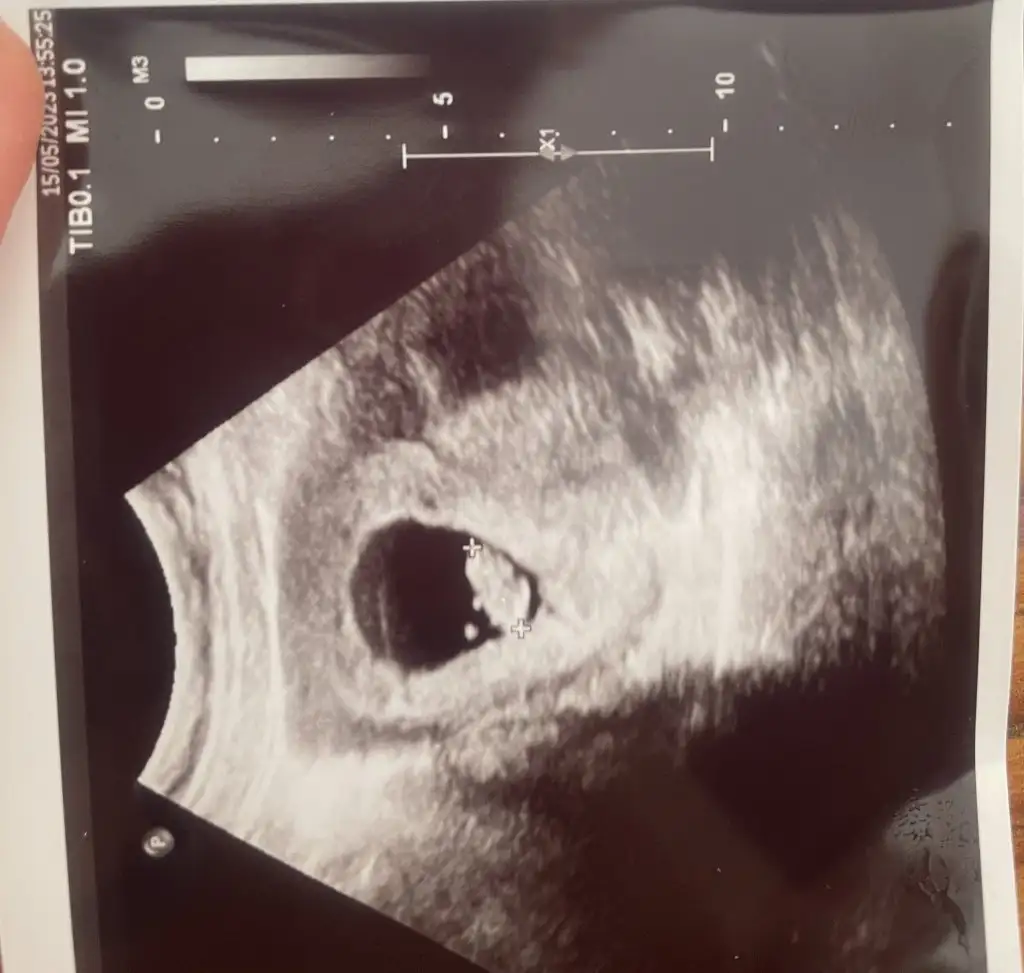

Kuzum tam ortada duruyor ya bilemedim yanlış bir şey söylemek istemiyorum 6 haftalım yok mu